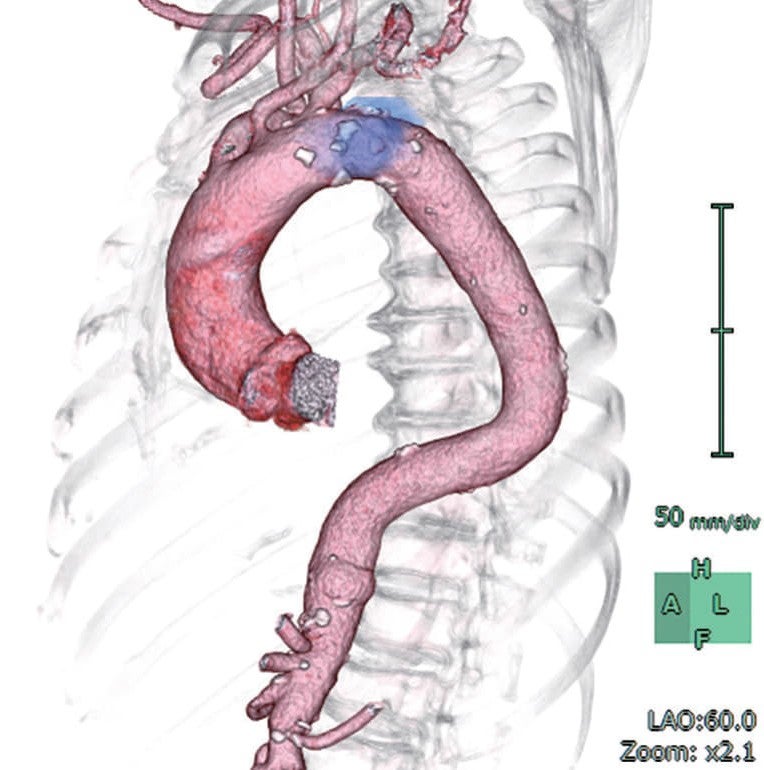

Image

Shaggy Aortaを合併した遠位弓部大動脈瘤に対するTEVAR

さらに詳しく